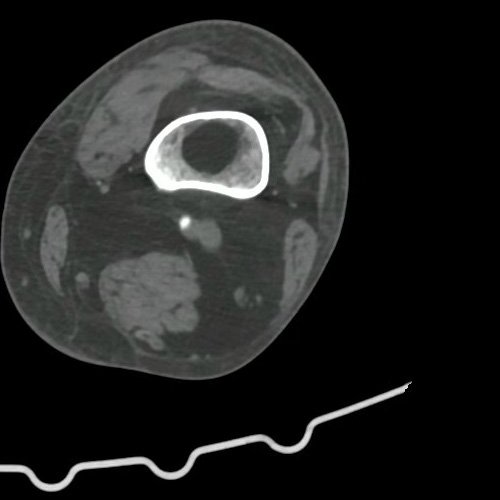

Imagen

Angio TAC de miembro inferior izquierdo con contraste EV corte coronal (DÍA 0)

• AngioTAC de miembro inferior izquierdo (DÍA 0):  No se observan alteraciones a nivel del fémur ni de las porciones visualizadas de la tibia y el peroné. No se observan alteraciones a nivel de los grupos musculares visualizados. La disposición del tejido graso es normal.  Arteria ilíaca interna: de calibre y trayecto conservado, permeable. Arterias ilíaca externa y femoral común: de calibre y trayecto conservados, permeables. Arterias circunfleja ilíaca superficial y epigástrica superficial: de calibre y trayecto conservados, permeables. Arteria femoral superficial: de calibre y trayecto conservado, permeable. Arteria femoral profunda: de calibre y trayecto conservado, permeable. Arterias circunflejas femoral medial y lateral: de calibre y trayecto conservados, permeables. Arteria poplítea: a 5 cm por encima del hueco poplíteo, se visualiza una irregularidad en la opacificación de la misma, con una  extensión aproximada de 1cm, no obstante se visualiza permeable. Se sugiere correlacionar con EcoDoppler arterial de miembros inferiores.  Arteria tibial anterior: de calibre y trayecto conservado, permeable. Arteria tibial posterior: de calibre y trayecto conservado, permeable. No es posible evaluar a las arterias tibial posterior y anterior hacia distal. Se sugiere cotejar con Ecodoppler. Informe definitivo pendiente

Curso internación en sala general para estudio de dolor y cianosis distal de pie izquierdo. Por dicho motivo se solicita eco doppler arterial de miembros inferiores, donde no se observaron signos  de estenosis hemodinámicamente significativa que justifique dicho cuadro. Se solicita evaluación por  servicio de hemodinamia, quienes sugieren realizar una angiotomografía de miembros inferiores. En este estudio se visualizó irregularidad en la opacificación de la arteria poplítea izquierda, pero sin embargo es permeable, por lo que servicio de hemodinamia desestima realizar arteriografía de urgencia. Se acuerda el inicio de tratamiento anticoagulante con enoxaparina  80 mg cada 12 hs y atorvastatina 80 mg/día y